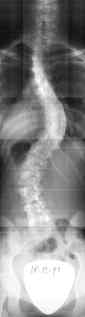

Al controllo clinico, il rachide risultava squilibrato verso destra di 1 cm., il triangolo della taglia più accentuato a destra, la spalla sinistra anteposta. Al bending test in flessione si evidenziava un gibbo dorsale destro di 1 cm e lombare sinistro di 0,5 mm. Fisiologica la lordosi lombare, ridotta la cifosi. Fu prescritto un radiogramma del rachide in antero-posteriore e in laterale, che evidenziava una scoliosi dorsale destra di 18° Cobb e lombare sinistra di 15°, con discreta rotazione vertebrale. Per le caratteristiche della scoliosi, nonostante la giovane età della paziente, viene prescritto un corsetto ortopedico tipo Milwakee, fisioterapia e controlli periodici.

Sebbene la paziente avesse seguito pedissequamente le indicazioni ricevute, ai controlli clinici e radiografici successivi la scoliosi non solo non migliorava, ma mostrava un carattere evolutivo con tendenza al peggioramento.

All’età di 11 anni veniva modificato il tipo di corsetto con un modello lionese; all’età di 12 anni, in corrispondenza del menarca, si verificava un ulteriore importante peggioramento della scoliosi, che arrivava a 42° Cobb dorsale e 34° lombare. Il dorso piatto peggiorava la prognosi.